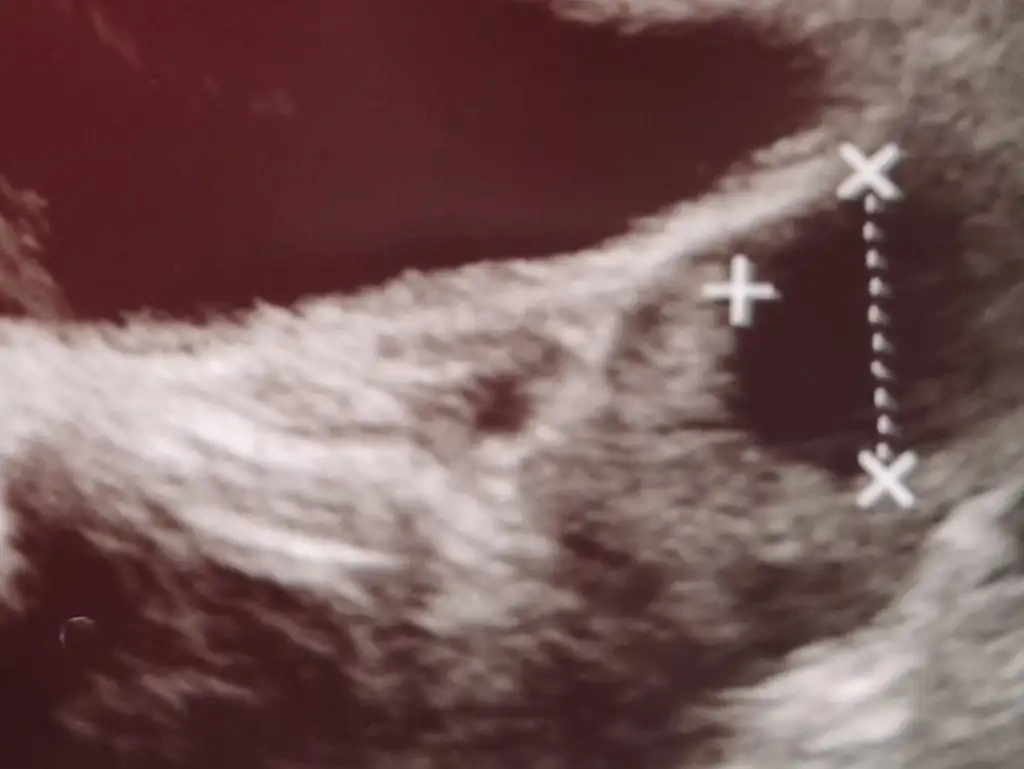

geç yumurtlama oluyor demekki canım . Adet düzensizliği var mı sende ama 15 mm de büyür önemli olan ilaçsızda yumurtan gelişmesiHayır kullanmadım, iyi bir değer mi? Döngünün 22. Günündeyim![]()

ultrason ortasını çeker misin canım . bu rakamlar 2 yumurtada olabilir ortalaması da olabilir. 2 yumurta ise eğer 21 ve 15 mm görünüyorDoktor 15 mm dedi kağıtta da böyle yazıyor canım.. Bakalım![]()

1 yumurtanın ölçüleri sanırımultrason ortasını çeker misin canım . bu rakamlar 2 yumurtada olabilir ortalaması da olabilir. 2 yumurta ise eğer 21 ve 15 mm görünüyor

Gözün aydın canım maşallahMerhaba bugün usg yaptırdım polikistik over veya herhangi bir kist yokmuş, folikül 15 mm olmuş, genelde günde 2 mm büyür, Salı günü tekrar bakalım dedi kızlar

Bu çapı ölçüyor sonra doktor yarı çapı için 2 ye bölüyor. 14 mm, 18mm falan hep yarı çap hesabı1 yumurtanın ölçüleri sanırım

eğer folikül 2 yerden çağı hemen hemen aynı ise direk yazan oluyor. bende hep hemen hemen tam yuvarlaktı. arkadaşta bi çağ 21.4 mm diğer yer 15.1 mm demekki ortalaması 15 mm olarak demişBu çapı ölçüyor sonra doktor yarı çapı için 2 ye bölüyor. 14 mm, 18mm falan hep yarı çap hesabı![]()

Aynen orda da doktor toplayıp ortalamasını alıyordu.eğer folikül 2 yerden çağı hemen hemen aynı ise direk yazan oluyor. bende hep hemen hemen tam yuvarlaktı. arkadaşta bi çağ 21.4 mm diğer yer 15.1 mm demekki ortalaması 15 mm olarak demiş

Ama bana göre arkadaşın ki 18 mm falan olması lazımAynen orda da doktor toplayıp ortalamasını alıyordu.

Yani benimki 15 demiBu çapı ölçüyor sonra doktor yarı çapı için 2 ye bölüyor. 14 mm, 18mm falan hep yarı çap hesabı![]()